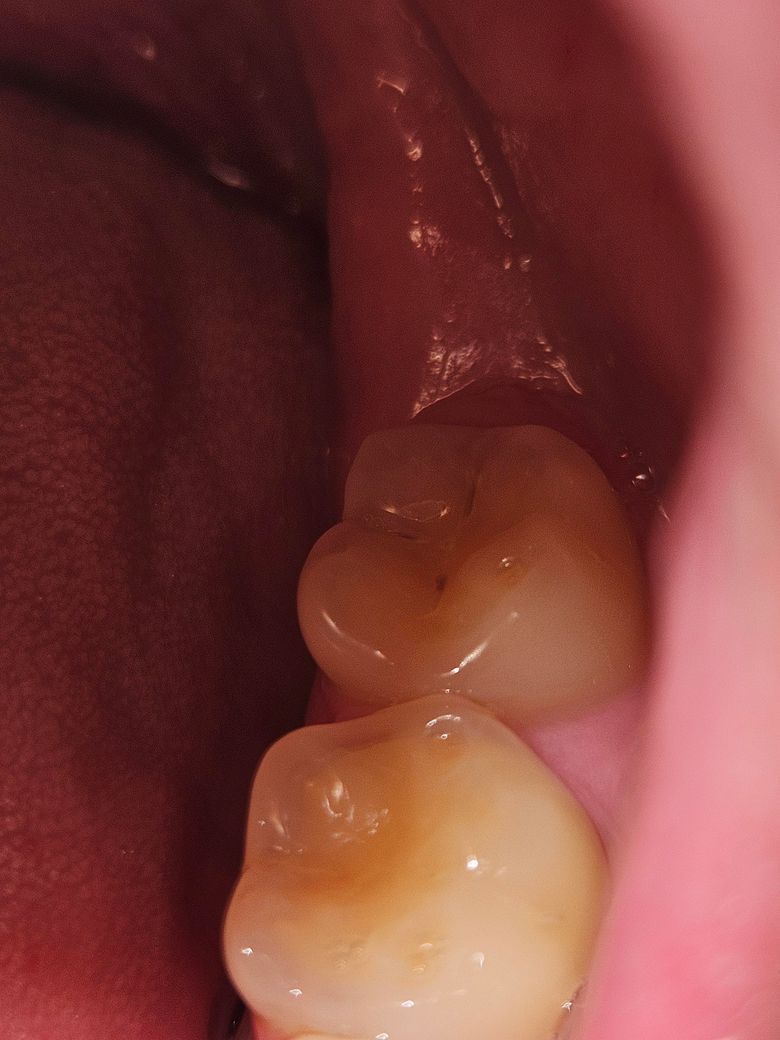

초기 충치 치료 반드시 받아야 할까요? 관리만으로 유지 가능할까요?

정기검진 받으면서 충치가 있어서 치료해야 한다고 하셨는데, 초기라서 마취없이 긁어내고 레진으로 치료하면 된다고 합니다. 근데 레진이 영구적이지는 않다고 해서, 뭔가 치아를 깍아내고 계속 주기적으로 충전재을 채워야 한다는 것에 약간 거부감이 드는데 꼭 치료를 해야하는 정도일까요? 나이는 만 24살입니다. 아픈느낌은 아예 없습니다. 1년에 스케일링 받는 주기를 6개월에 한번씩 하는걸로는 안 될까요?

사진으로 봤을 경우에는 충치가 그렇게 커보이지는 않습니다 충치가 진행이 되는것이 아니라면 관리를 하면서 사용을 할수도 있습니다.

1. 엑스레이를 찍어봐야 정확히 알겠지만 위 사진만으론 치료가 필요한 정도의 충치는 아닐 것 같습니다.